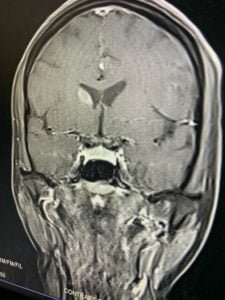

Case of the month: MELAS

A 35 year old female with infertility presented with seizure disorder. MRI brain showed flair hyperintensity in frontal ,parietal lobe and occipital frontal gyrus and olfactory gyrus . With enhancement in right caudate head and left occipital lobe Leptomeningeal enhancement in Parietal lobes .

Final diagnosis of MELAS ( Mitochondrial Encephalomyopathy, Lactic Acidosis, Strokelike Episodes )